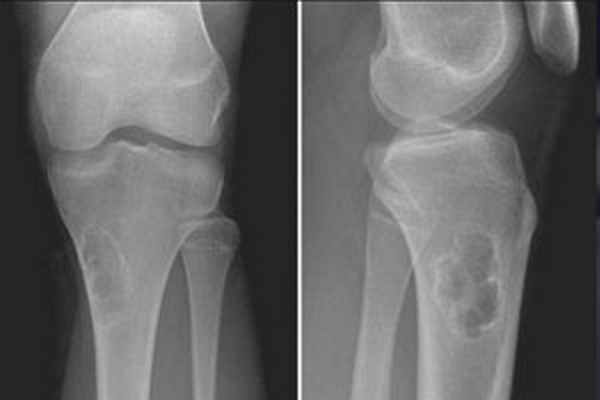

• Хрящевой матрикс присутствует редко (<10%)(Слева) Рисунок: макроскопические особенности хондромиксоидной фибромы (ХМФ). Хорошо отграниченный блестящий мясистый очаг. Очаг расположен эксцентрично и способствует небольшому вспучиванию кортикального слоя.

(Справа) Рентгенография типичной ХМФ в ПЗ проекции. Метафизарный, эксцентрично расположенный патологический очаг чаще всего обнаруживается в большеберцовой кости и характеризуется небольшой пузырчатостью и склеротическим краем. Как показывает данная рентгенография ХМФ не обязательно содержит хрящевой матрикс. (Слева) Рентгенография в ПЗ проекции: необычная ХМФ у маленького ребенка. Этот центрально расположенный метафизарный очаг лучевой кости больше походит на аневризмальную костную кисту, однако ХМФ была подтверждена результатами биопсии. Обратите внимание на псевдотрабекулярность, придающую патологическому очагу перегородчатый вид.